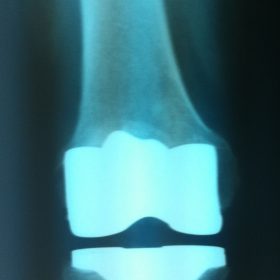

Διάγνωση- Σταδιοποίηση

Διακρίνονται σε 4 στάδια.

Στάδιο Ι. Στένωση του μεσαθριου διαστήματος

Στάδιο ΙΙ. Σκλήρυνση του υποκύμενου χόνδρου

Στάδιο ΙΙΙ. Σκλήρυνση του υπερκείμενου χόνδρου, καταστροφή του υποχόνδρινου οστούν, σχηματισμός οστεόφυτων, οίδημα αρθρώσεως και βραδυνός πόνος

Στάδιο IV. Οστική καθίζηση, καταστροφή μαλακών μορίων μυϊκών ομάδων, υπεξάρθρημα της αρθρώσεως και αλλαγή του μηχανικού άξονα